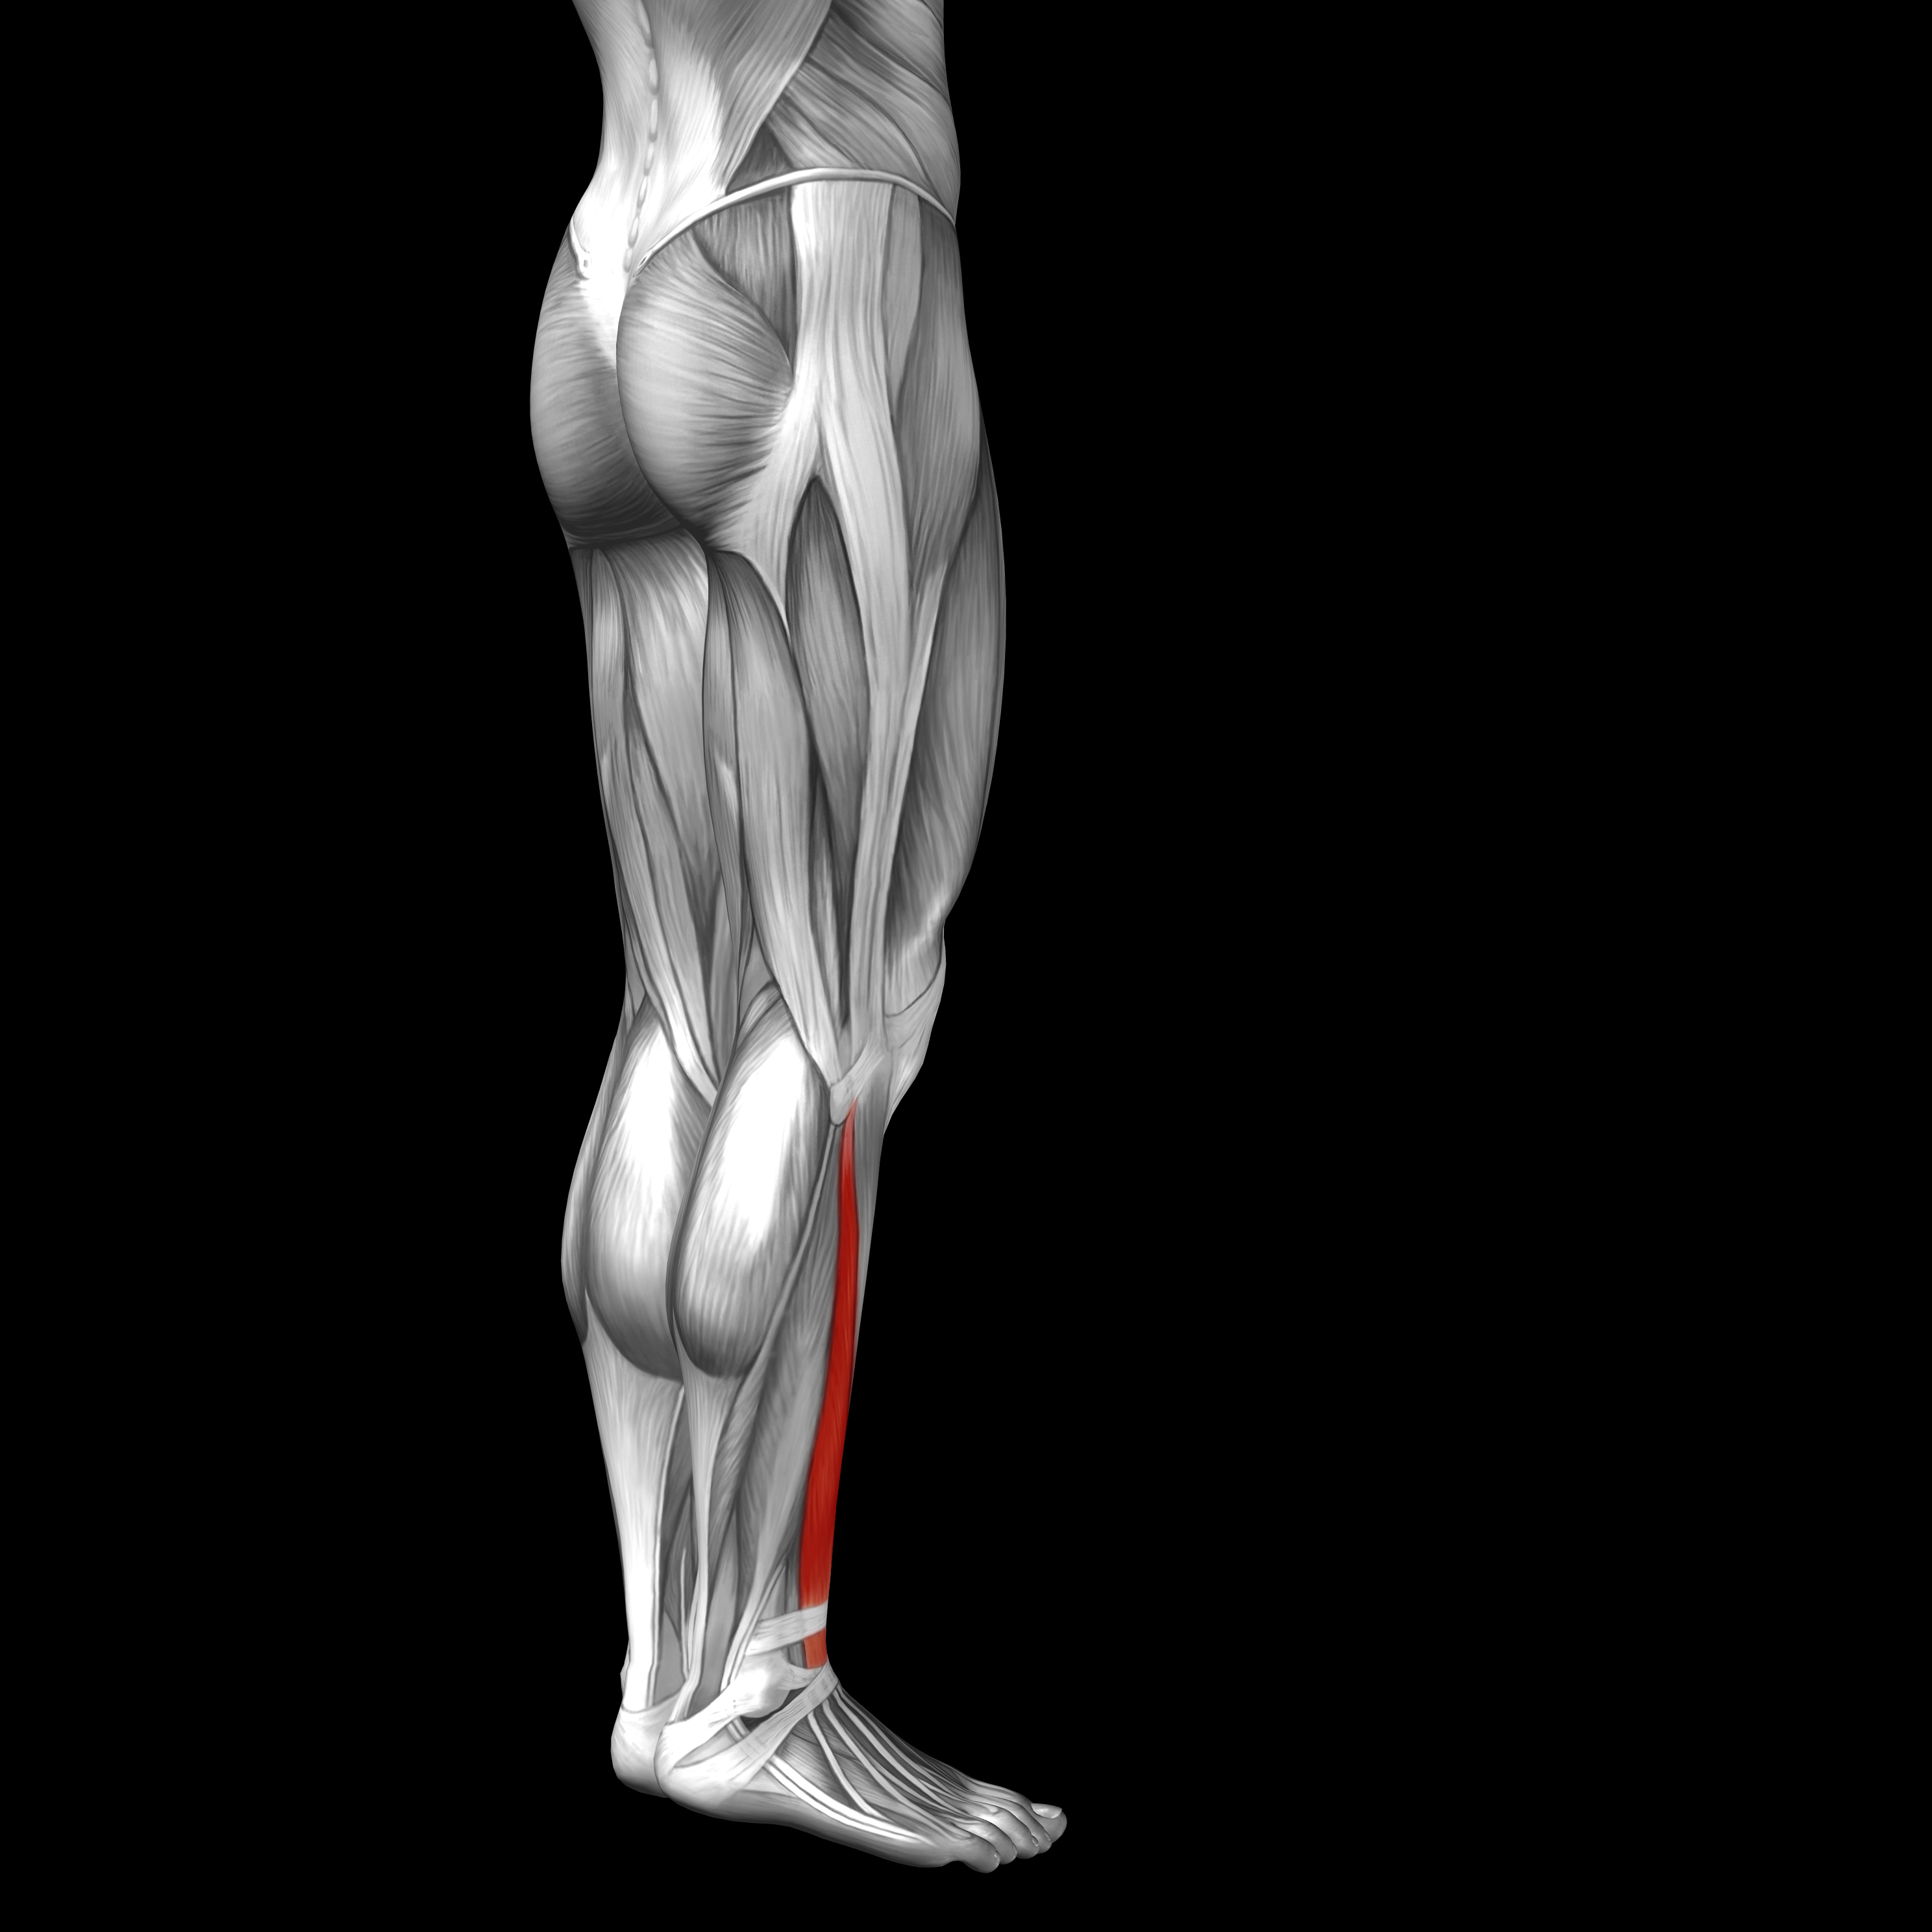

Анатомия и Функции Мышцы Adductor Magnus